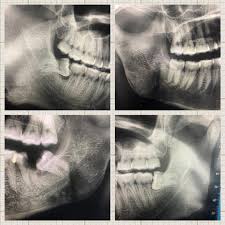

- Bước 1: Khám và chụp x-quang

Bác sĩ sẽ khám tổng quát và chụp x-quang để biết xác định tình trạng răng miệng của bạn, cấu trúc xương hàm và vị trí dây thần kinh xung quanh răng cần nhổ. Đây là bước rất quan trọng nếu chẩn đoán không chính xác sẽ dễ dẫn đến những biến chứng nguy hiểm.